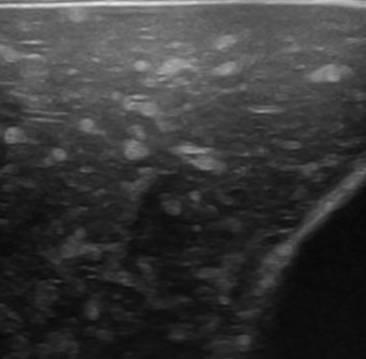

Hamartoma đường mật

» Thông tin: Nam giới – 39 tuổi.

» Lâm sàng: Kiểm tra sức khỏe.